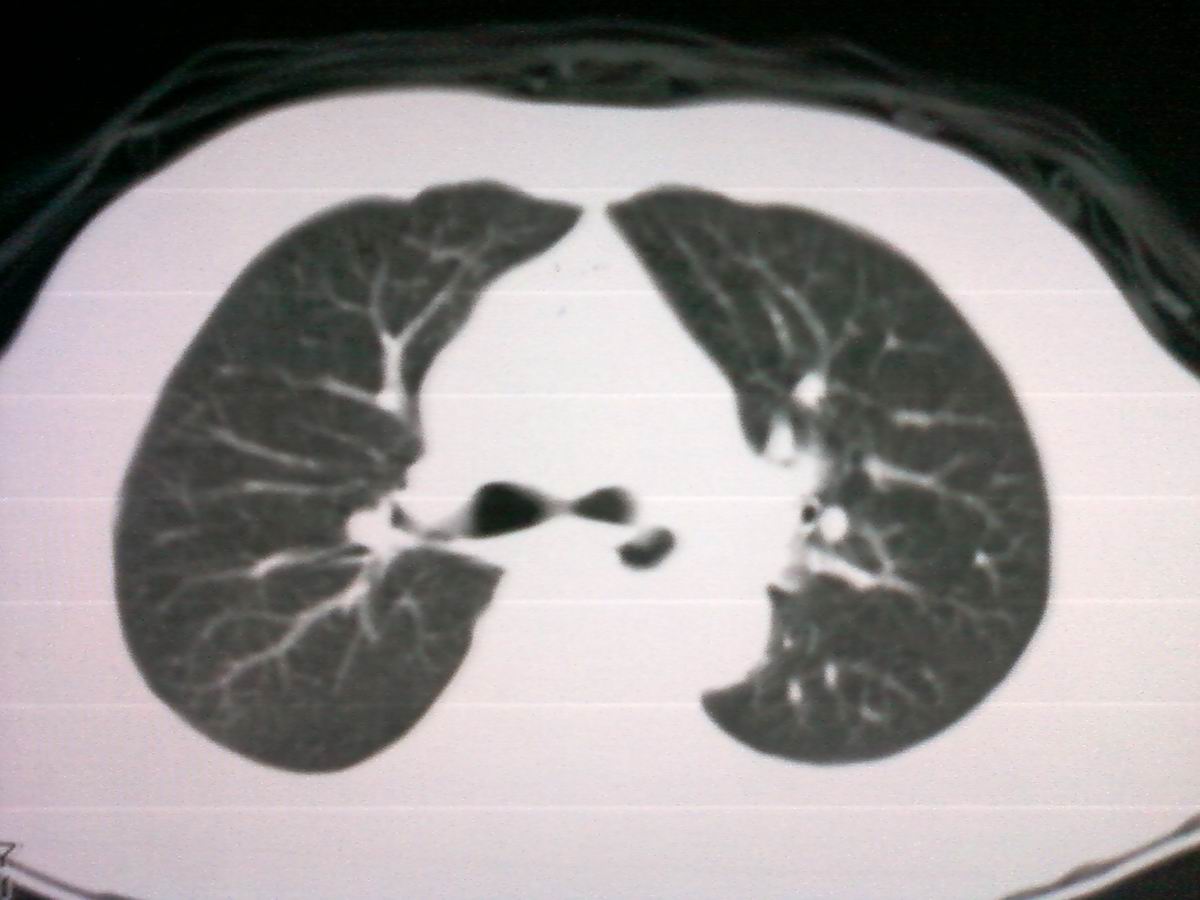

支管占位,建议作支纤镜检查及活检。

考虑气管癌可能性大。